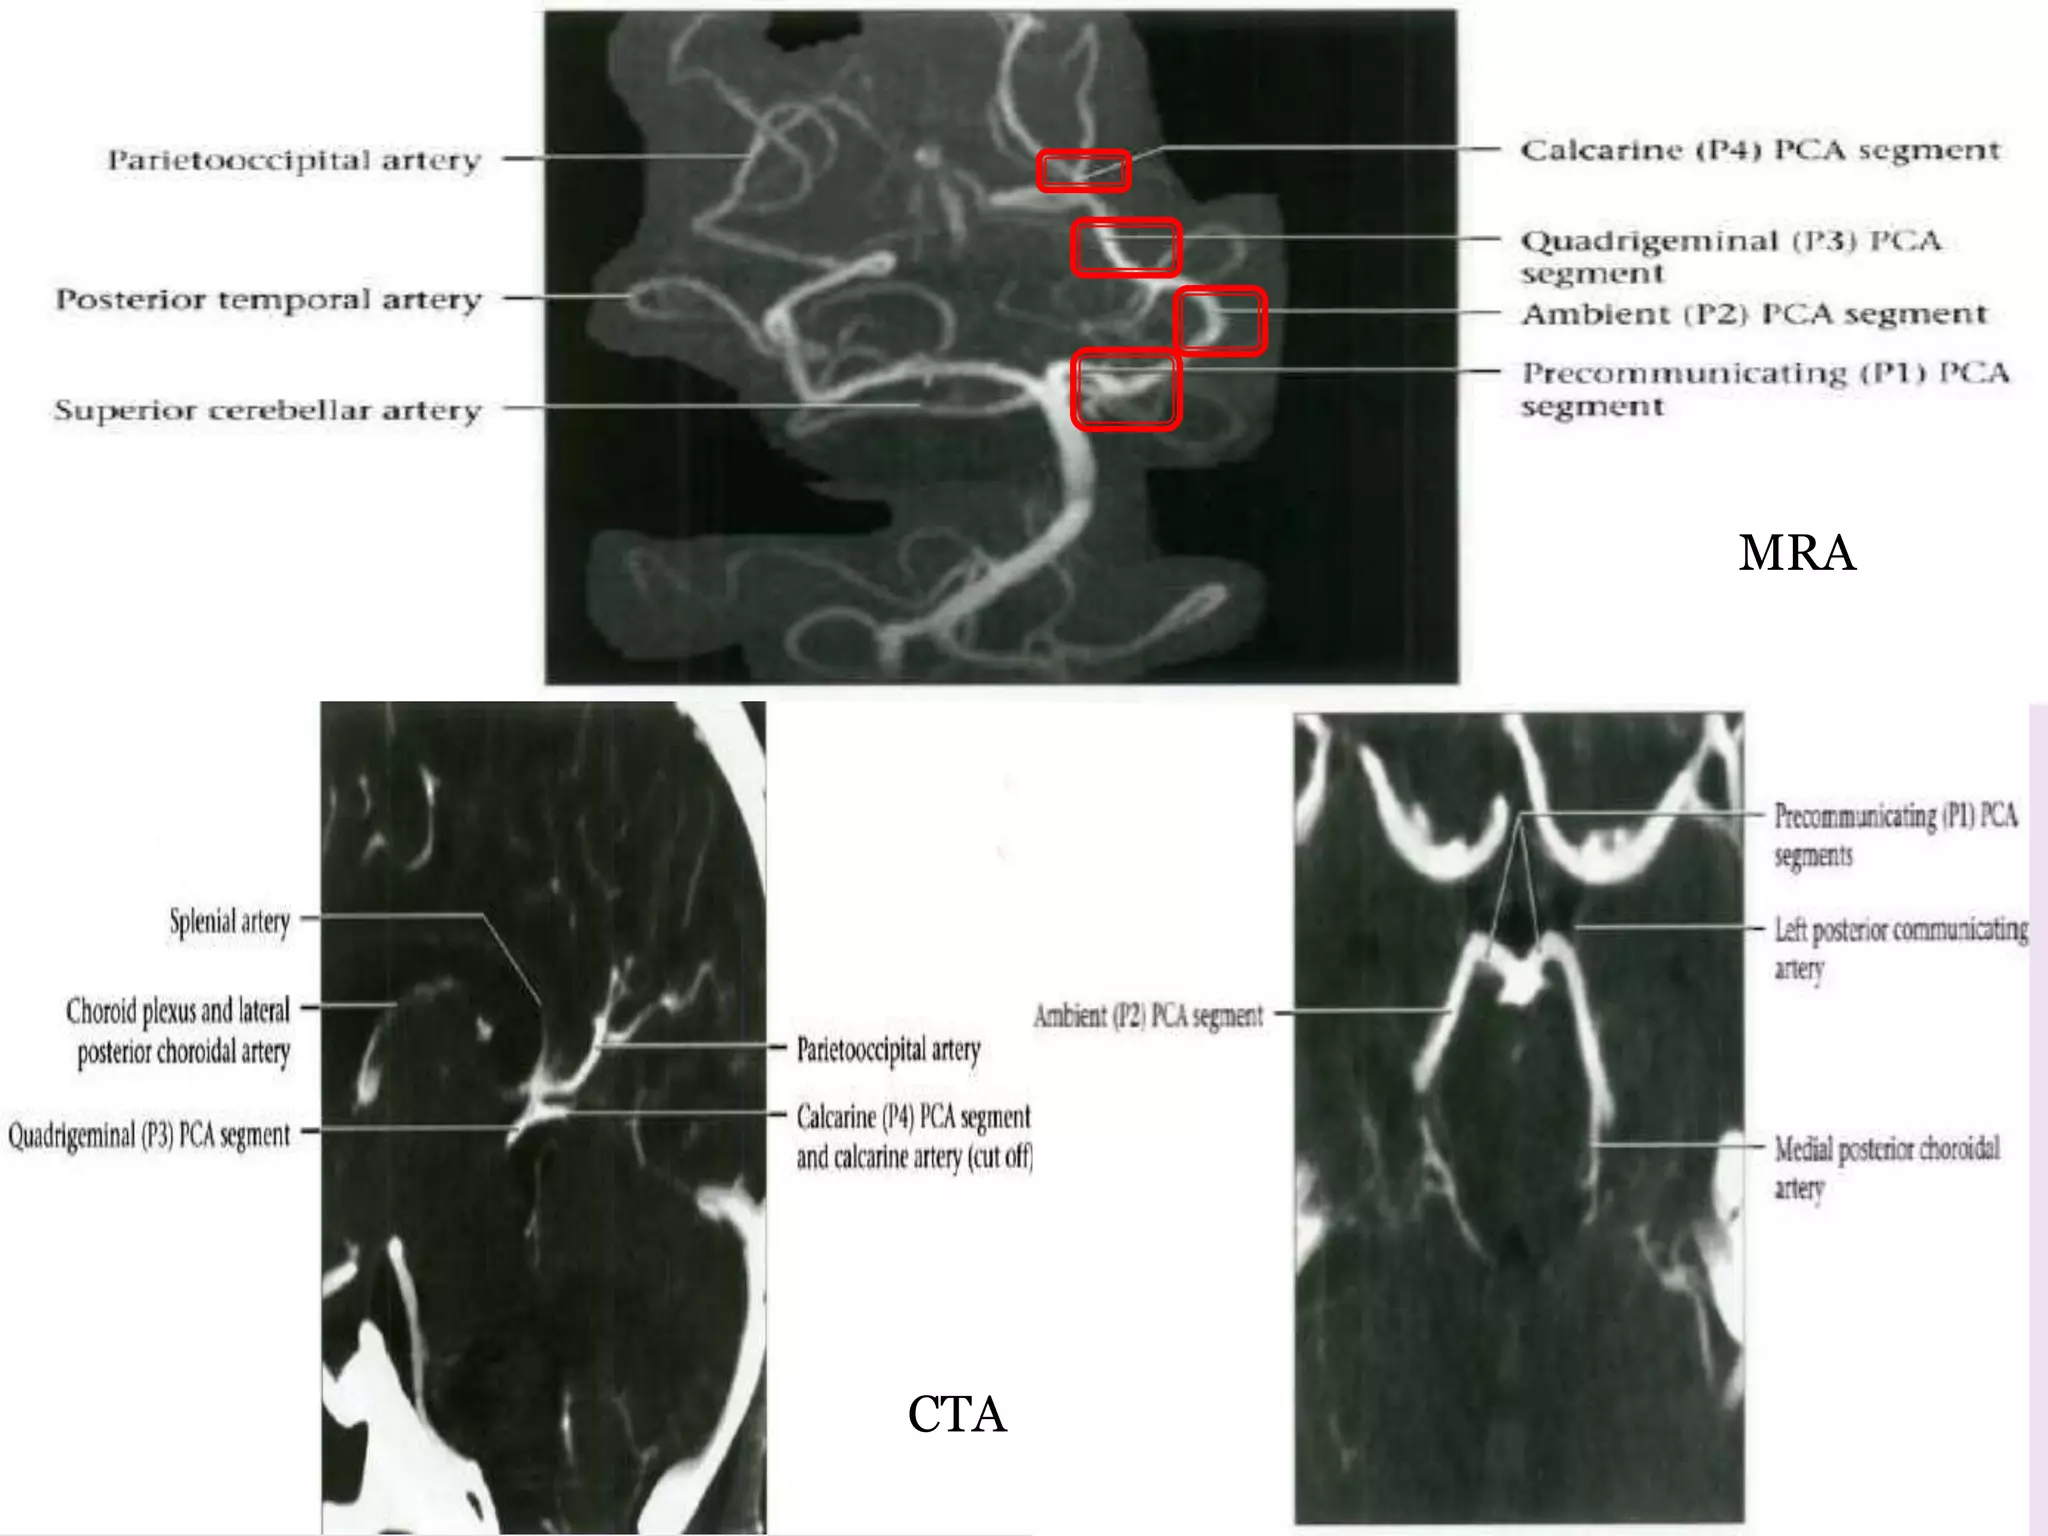

MRA

CTA

PCA origin from bifurcation of basilar artery in interpeduncular cistern.

P1 precommunicating /

P2 ambient / crural

P3 quadrigeminal

Parietooccipital artery

Calcarine artery( P4 )

Posterior pericollasal artery

PCA origin frombifurcation of basilar artery in interpeduncular cistern. Lies above occulomotar nerve. Circles midbrain above tentorium cerebelli.

P1 precommunicating / peduncular •Basilar bifurcation extends laterally • Junction with PCoA • Br – • Post thalamoperforating- thalamus , midbrain • Medial posterior choroidal artery – anteromedially along roof of 3rd ventricle – tectal plate , midbrain , thalamus posterior , pineal gland , tele choroidae of 3rd ventricle. P2 ambient / crural • PCA- PCoA junction posterior • Above trochlear nerve and tentorial incisura • Br – • Thalamogeniculate arteries- MGB , pulvinar , brachium superior colliculus , crus cerebri , LGB • Lateral post choroidal artery – over pulvinar of thalamus – posterior thalamus , lateral ventricular choroid plexus

P3 quadrigeminal Behind midbrainin quadrigeminal plate cistern Reciprocal relationship with MCA Inferior temporal artery • Undersurface of temporal bone • Anastamose -MCA Parietooccipital artery • Posterior 1/3rd interhemispheric surface • ACA Calcarine artery( P4 ) • Visual cortex • Occipital pole Posterior pericollasal artery (splenial) • Splenium of corpus callosum • ACA

• Supply – •Medial +posterior temporal lobe • Medial parietal lobe • Occipital lobe